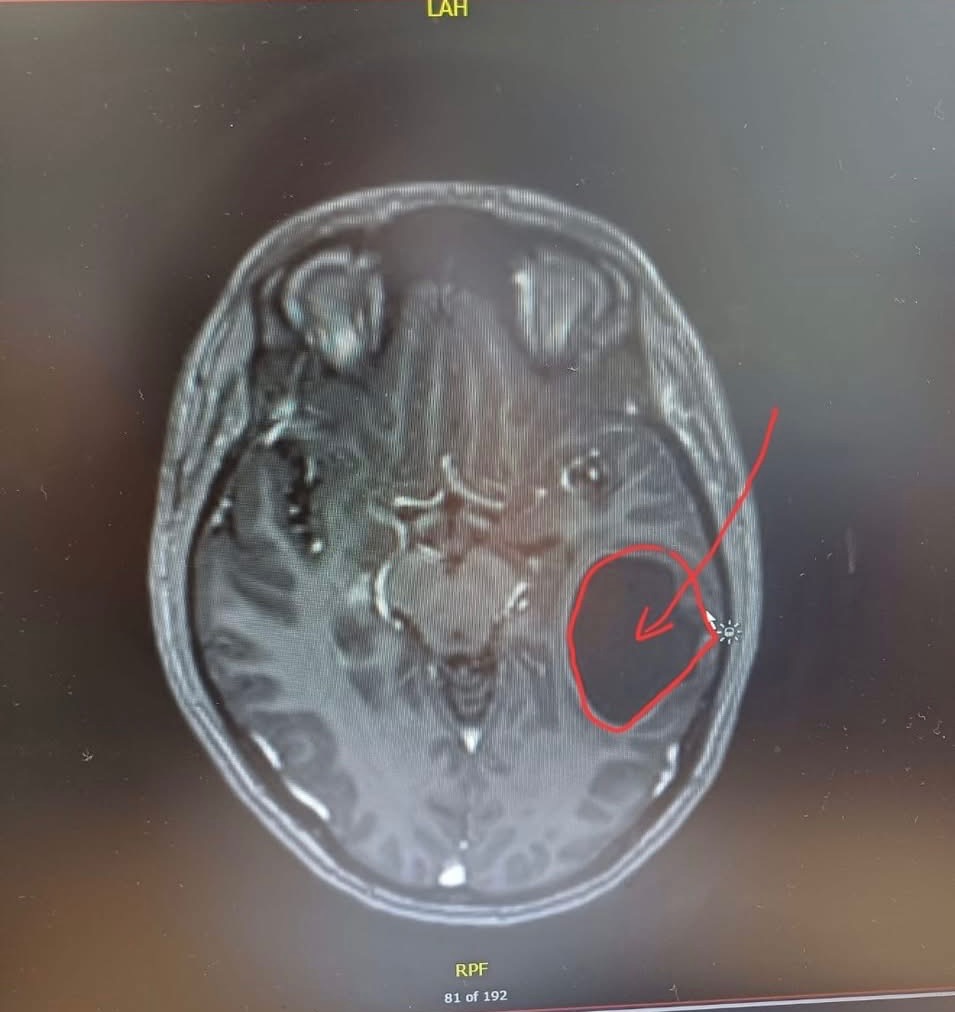

In August 2025 we received the catastrophic news that our friend, partner, daughter, Lou was diagnosed with an agressive Grade 4 Glioma/Glioblastoma (brain cancer) after discovering a large tumour.

The tumour was removed, but Lou has been told that it will return because of its agressive nature. Its just a matter of when. There is apparently no cure for this.